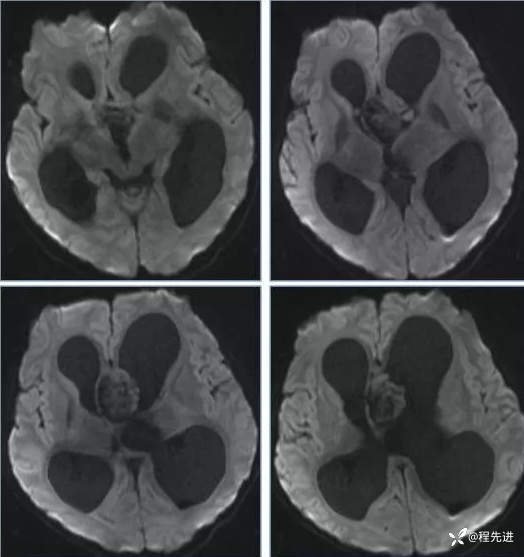

【神经】特别精彩病例|行走不稳2月余

患者性别:男

患者年龄:13岁

主诉:行走不稳2月余

现病史:2个月前患者无明显诱因下出现行走不稳,近期症状逐渐加重,站立不能。病程中患者无意识障碍,无头痛头晕,无明显恶心呕吐、视物旋转、耳鸣、眼球活动障碍等,无尿量增多、泌乳、口干等,体重无明显改变,睡眠可,食欲可,二便正常。

专科检查:右侧肢体肌力III-IV级,左侧肢体肌力IV级,肌张力下降